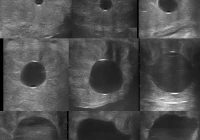

Mare Ultrasound Pregnancy Images

Equine Ultrasound Pregnancy Images – Serial ultrasound images of early pregnancy in the mare. Discussion of variations and differences between stages seen in the images. All of the mare ultrasound pregnancy images and videos below were produced using a Universal S8 Color Doppler Ultrasound from Universal Imaging, Bedford Hills, NY. Click on all images to see an enlargement For… Read More »